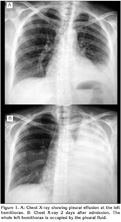

Within 48 hours her condition improved and her temperature returned to normal. Intravenous ampicillin was continued at the higher dose for 10 days and followed by one week of oral ampicillin, 2 g daily. The patient was discharged without any medication on the 18th postoperative day. Six weeks after admission her radiograph is clear, while she is asymptomatic (Figure 3).

Figure 3